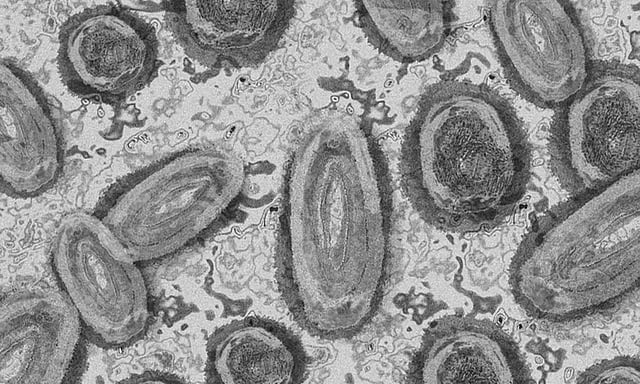

Study decodes how mpox virus infiltrates brain cells

TORONTO: Mpox (Monkeypox) virus may be infiltrating cells responsible for normal brain functioning causing neurological symptoms in people affected by the virus, finds a study.

Researchers from the University of Alberta used laboratory experiments to infect human brain cells with the mpox virus.

In a newly published research in the journal Proceedings of the National Academy of Sciences, the team found mpox virus infiltrated the astrocytes -- a type of cell responsible for normal brain function -- triggering an extreme immune response.

"We found that monkeypox virus can efficiently infect these cells and can induce a kind of brain cell death we call pyroptosis."